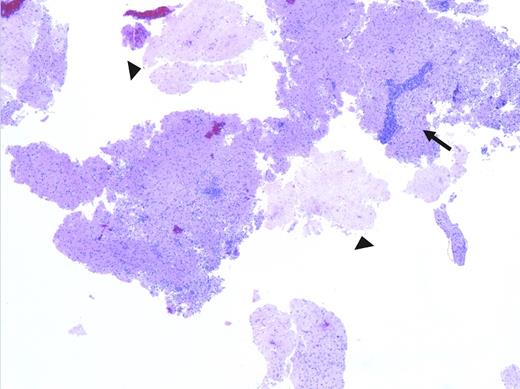

Low-power pathologic image showing fragments of brain tissue with areas of necrosis (arrowheads), as well as a patchy lymphoid infiltrate, including distinctly perivascular infiltrates (arrow).

A low-power image (Figure 2) shows fragments of brain tissue with areas of necrosis (arrowheads), as well as a patchy lymphoid infiltrate, including distinctly perivascular infiltrates (arrow). The arrowed area is shown at higher power in Figure 3. There is a dense lymphoid infiltrate surrounding the blood vessel, composed of small to medium-sized lymphocytes with condensed chromatin and variably irregular nuclei. Immunohistochemistry demonstrated that the lymphocytes were almost entirely CD3+ and CD5+, with a predominance of CD8+ over CD4+ cells; few CD20+ cells were present. They were negative for CD34, TdT, and CD117. The infiltrate was also negative for EBER. Additionally, there is a round structure seen to the left of the blood vessel, which is enlarged in Figure 4.

The round structure in Figures 3 and 4 represents a classical toxoplasmosis cyst, formed due to the host’s immune response to this organism. Multiple such structures were encountered in this biopsy. Toxoplasma cysts consist of bradyzoites aggregated within a membrane-bound cystic structure and are essentially diagnostic of Toxoplasma gondii. It usually is seen in the latent or chronic forms of infection and tends not to elicit an immune response, though in this case it is evident in an active tissue infection. The diagnosis of toxoplasmosis was also confirmed in this case by a positive qualitative polymerase chain reaction CSF test, which has a high degree of specificity.